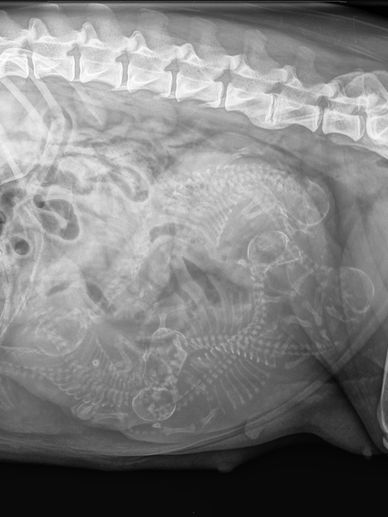

Jinsha hatte heute einen Termin fürs Röntgen. Die Tierärztin war

sehr zufrieden. Wir sind sehr glücklich und sehen gespannt auf die nächsten Tage. Wünscht uns Glück für die Geburt!